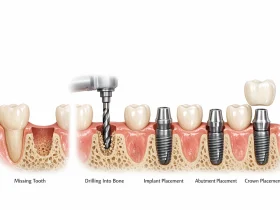

وقتی یک یا چند دندان از دست میرود، جایگزینی آن ضروری است تا کیفیت جویدن، گفتار، زیبایی لبخند و سلامت استخوان فک حفظ شود. ایمپلنت دندان یکی از رایجترین راههای جایگزینی است که با قرار دادن یک پایه مصنوعی در استخوان فک انجام میشود. این روش مزایایی مثل ثبات، طول عمر زیاد و عملکرد طبیعی دارد، اما شرایطی مثل هزینه بالا، نیاز به جراحی، یا عدموجود بافت استخوان کافی میتواند باعث شود فرد به دنبال روشهای کاشت دندان بدون ایمپلنت باشد. روشهایی که بدون نیاز به قرار دادن پایه ایمپلنت در استخوان انجام میشوند، در بسیاری از موارد گزینهای مناسبتر و کمتهاجمی برای بیماران هستند.

در دندانپزشکی مدرن روشهایی وجود دارند که میتوانند فضای خالی دندان از دست رفته را پر کنند، بدون آنکه پیچ یا پایه ایمپلنت در استخوان قرار داده شود. در ادامه مهمترین گزینهها را بررسی میکنیم.

بریج دندان (Dental Bridge)

بریج یکی از شناختهشدهترین روشهای جایگزینی دندان بدون ایمپلنت است. در این روش، دو دندان سالم کنار فضای خالی آماده میشوند و دندان مصنوعی بین این دو قرار میگیرد تا جایگزین دندان ازدسترفته شود.

چگونه انجام میشود؟

در بریج کلاسیک، دندانپزشک دو دندان مجاور فضای خالی را تراش میدهد تا بهعنوان پایه برای نگهداشتن پل مصنوعی عمل کنند. سپس دندانهای مصنوعی (پل) روی این پایهها قرار میگیرند.